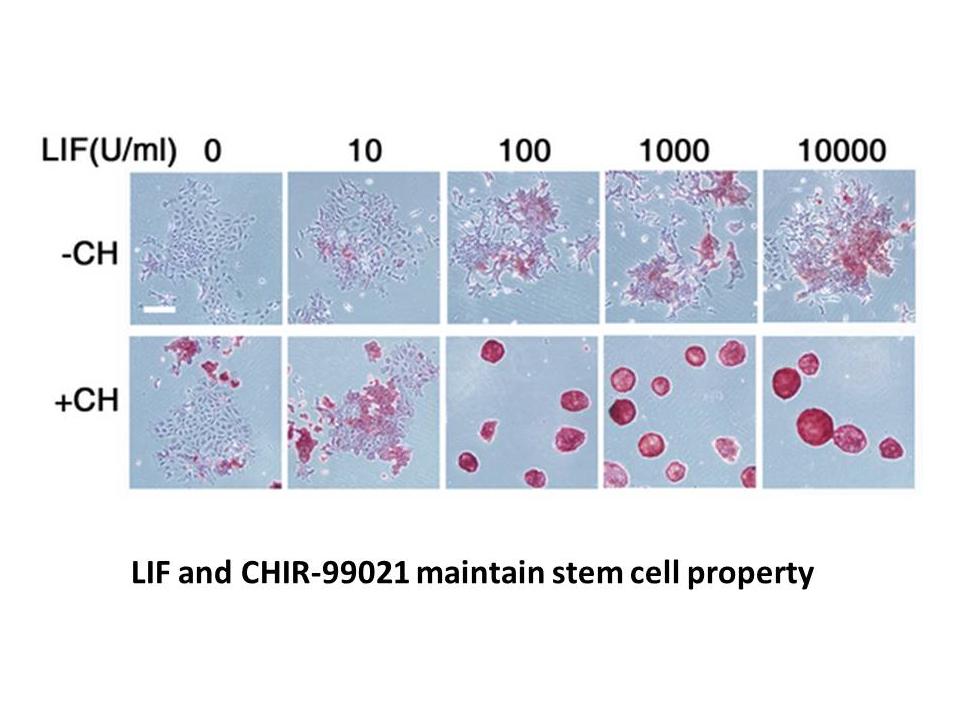

ONC201 Looks to Prove Efficacy in Trial For Rare H3K27M, APExBIO - CHIR-99021 (CT99021)|GSK-3 inhibitor, Cell,

APExBIO - CHIR-99021 (CT99021)|GSK-3 inhibitor, Cell,[A11103243]Fundamentals of Inorganic Glasses [ハードカバー] Varshneya, Arun K.